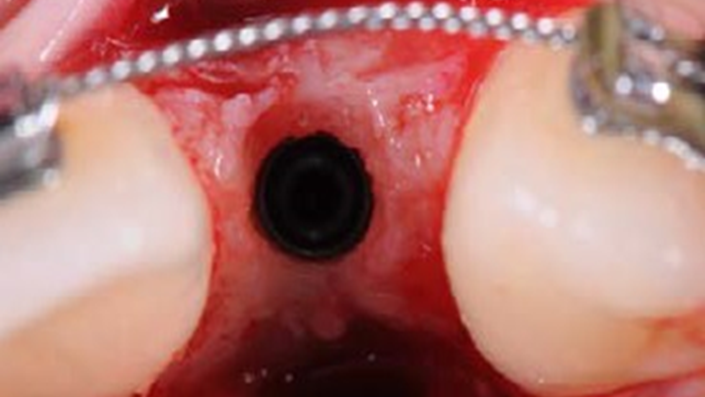

Clinical case: Patient-centered approach: treatment strategy for Root Membrane Technique & delayed implant placement

- Courtesy of Dr. Yoshiharu Hayashi, Japan -

Socket Shield Technique, anterior esthetics, maxillary anterior, esthetic, esthetics, delayed implant placement, socket preservation, AnyRidge, Root Membrane Kit, Root Membrane Technique, Partial Extraction Therapy, PET, esthetic zone, fuse abutment, Dr. Yoshiharu Hayashi,#11,#21,#22

AnyRidge implant system, fuse abutment Root membrane kit, PET Kit